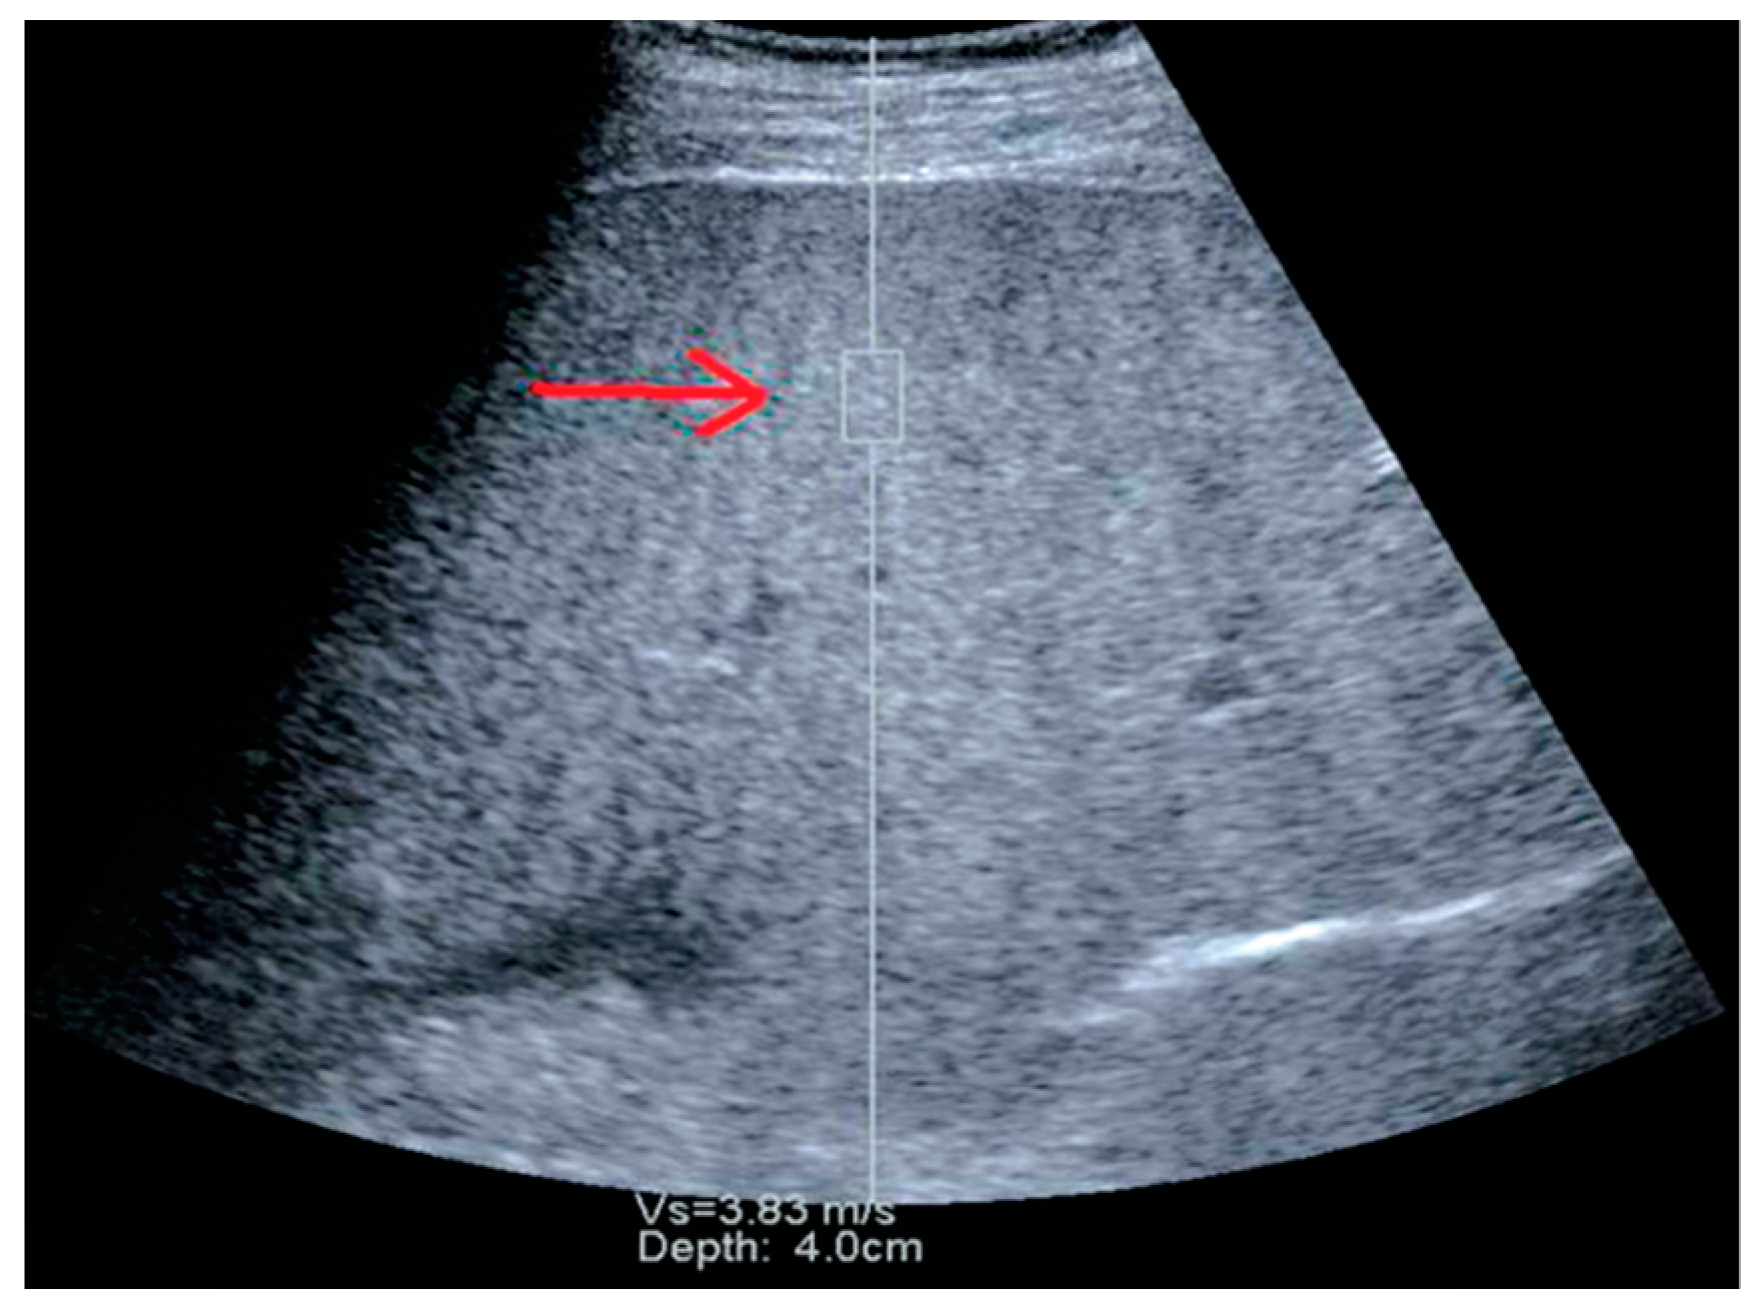

2.2. Point Shear Wave Elastography (pSWE)

Performance of pSWE for Liver Fibrosis Assessment in NAFLD and NASH